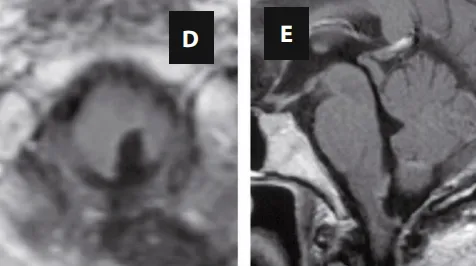

经头颅磁共振检查后,病因得以明确:延髓下部髓内发现大型肿瘤病灶,并已延伸至右侧小脑下脚。这个位于生命中枢(脑干)区域的肿瘤,正是导致长期顽固性呃逆的根本原因。肿瘤持续刺激或压迫控制打嗝反射的神经通路,引发了这一系列症状。

术前影像学评估

MRI检查(A-C序列)清晰显示肿瘤范围与毗邻关系。

面对这一位于手术禁区的复杂病变,INC的巴特朗菲教授为患者制定了精密的手术方案。主刀医生采用后正中入路行肿瘤切除术,在持续术中神经电生理监测的保驾护航下,精准完成肿瘤切除,彻底解除导致呃逆的病因。术后影像学检查证实肿瘤切除效果满意。